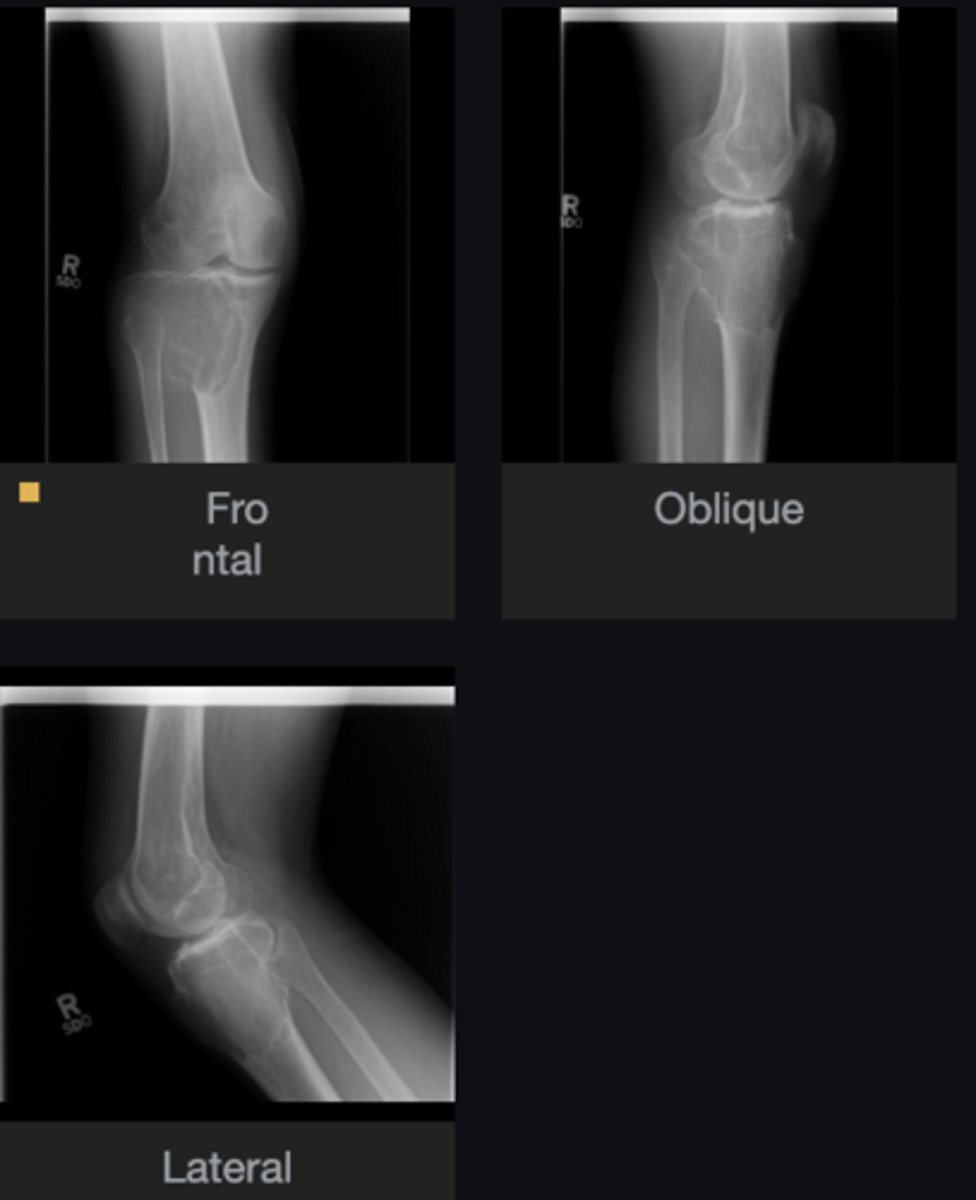

- Distal femur

- Metaphysis

- Anterolateral

- Broad base

- Cortex and medulla continuous

Describe the bone lesion

<p>Describe the bone lesion</p>

19

New cards

Sessile solitary osteochondroma

Most likely diagnosis?

<p>Most likely diagnosis?</p>

20

Hereditary multiple exostoses

21

Malignant transformation (5-25%)

Concerns/complications?

<p>Concerns/complications?</p>

22

Inherited metaphyseal overgrowth

How do you get this?

<p>How do you get this?</p>